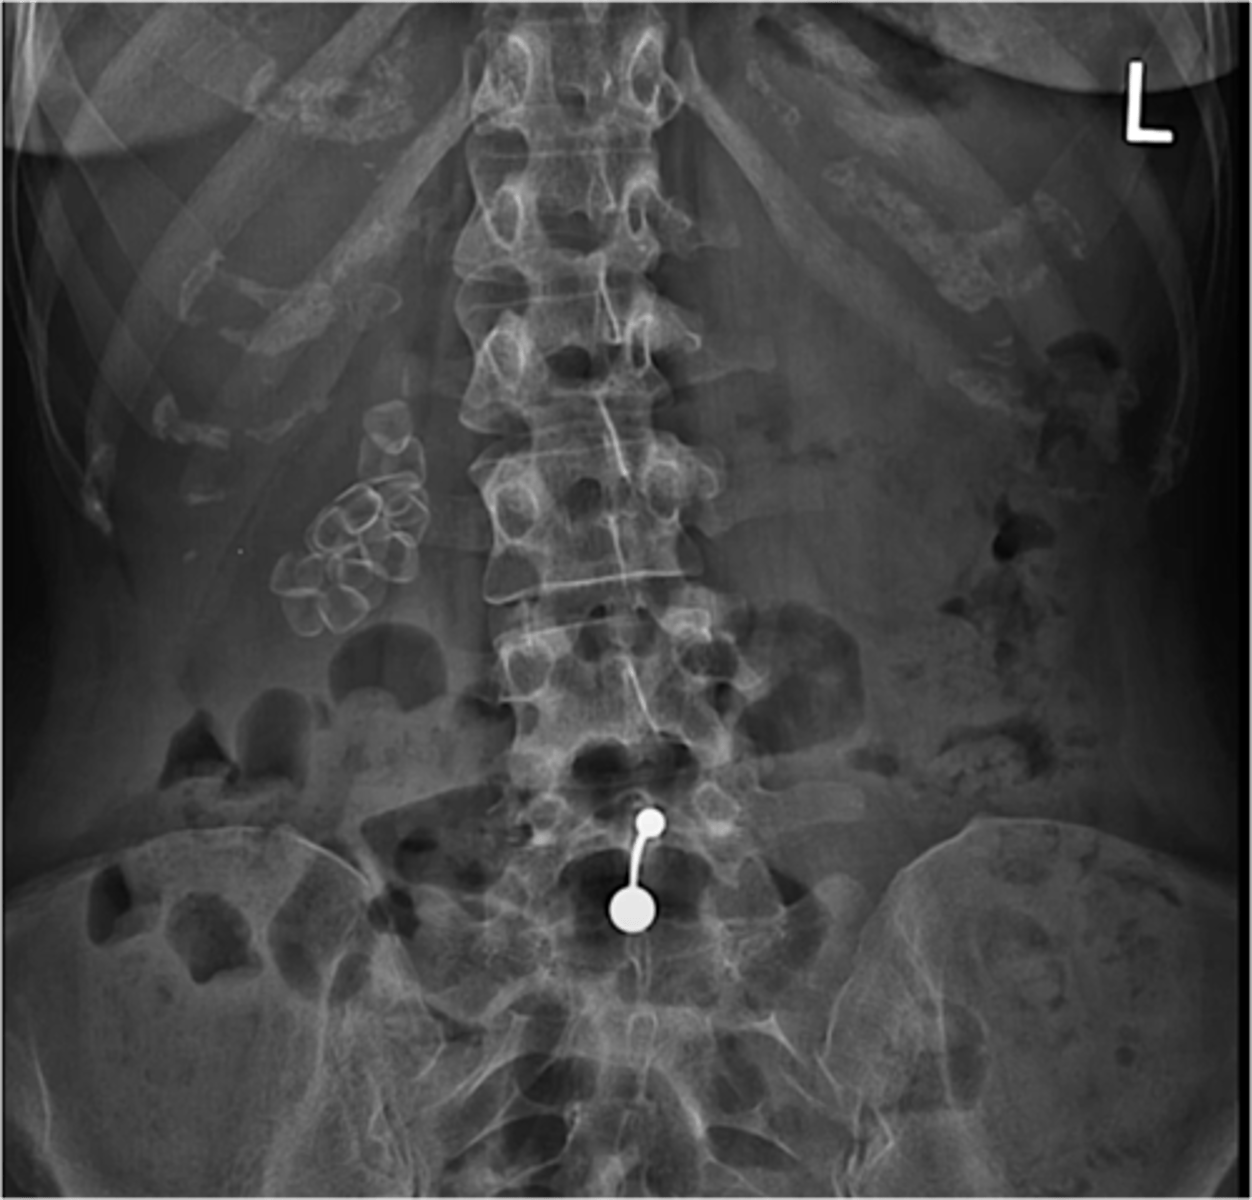

Kidney stones

Kidney stones (pic 2)

kidney stones (pic 3)